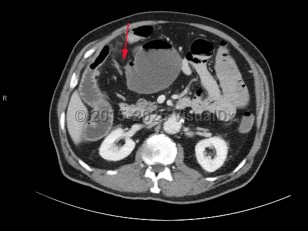

Patients most commonly present with diffuse or periumbilical abdominal pain, often described as colicky, with paroxysms every few minutes. Pain may become localized or constant if the bowel becomes ischemic or perforated. Abdominal distension is highly suggestive, as is constipation. Patients commonly have nausea and vomiting, which varies in severity based on the location of the obstruction, with proximal SBOs presenting with more severe symptoms. Patients with complete obstructions stop passing stool or flatus, although this may be delayed for 12-24 hours as the bowel distal to the obstruction continues to pass contents. Rarely, patients may have intermittent obstruction, often partial and low-grade, with spontaneous resolution of symptoms between episodes.

The greatest concern from an SBO is the risk of increased dilation leading to necrosis and bowel perforation. Patients with bowel ischemia or perforation typically present with more severe signs and symptoms, often with evidence of peritonitis, sepsis, and hemodynamic instability.